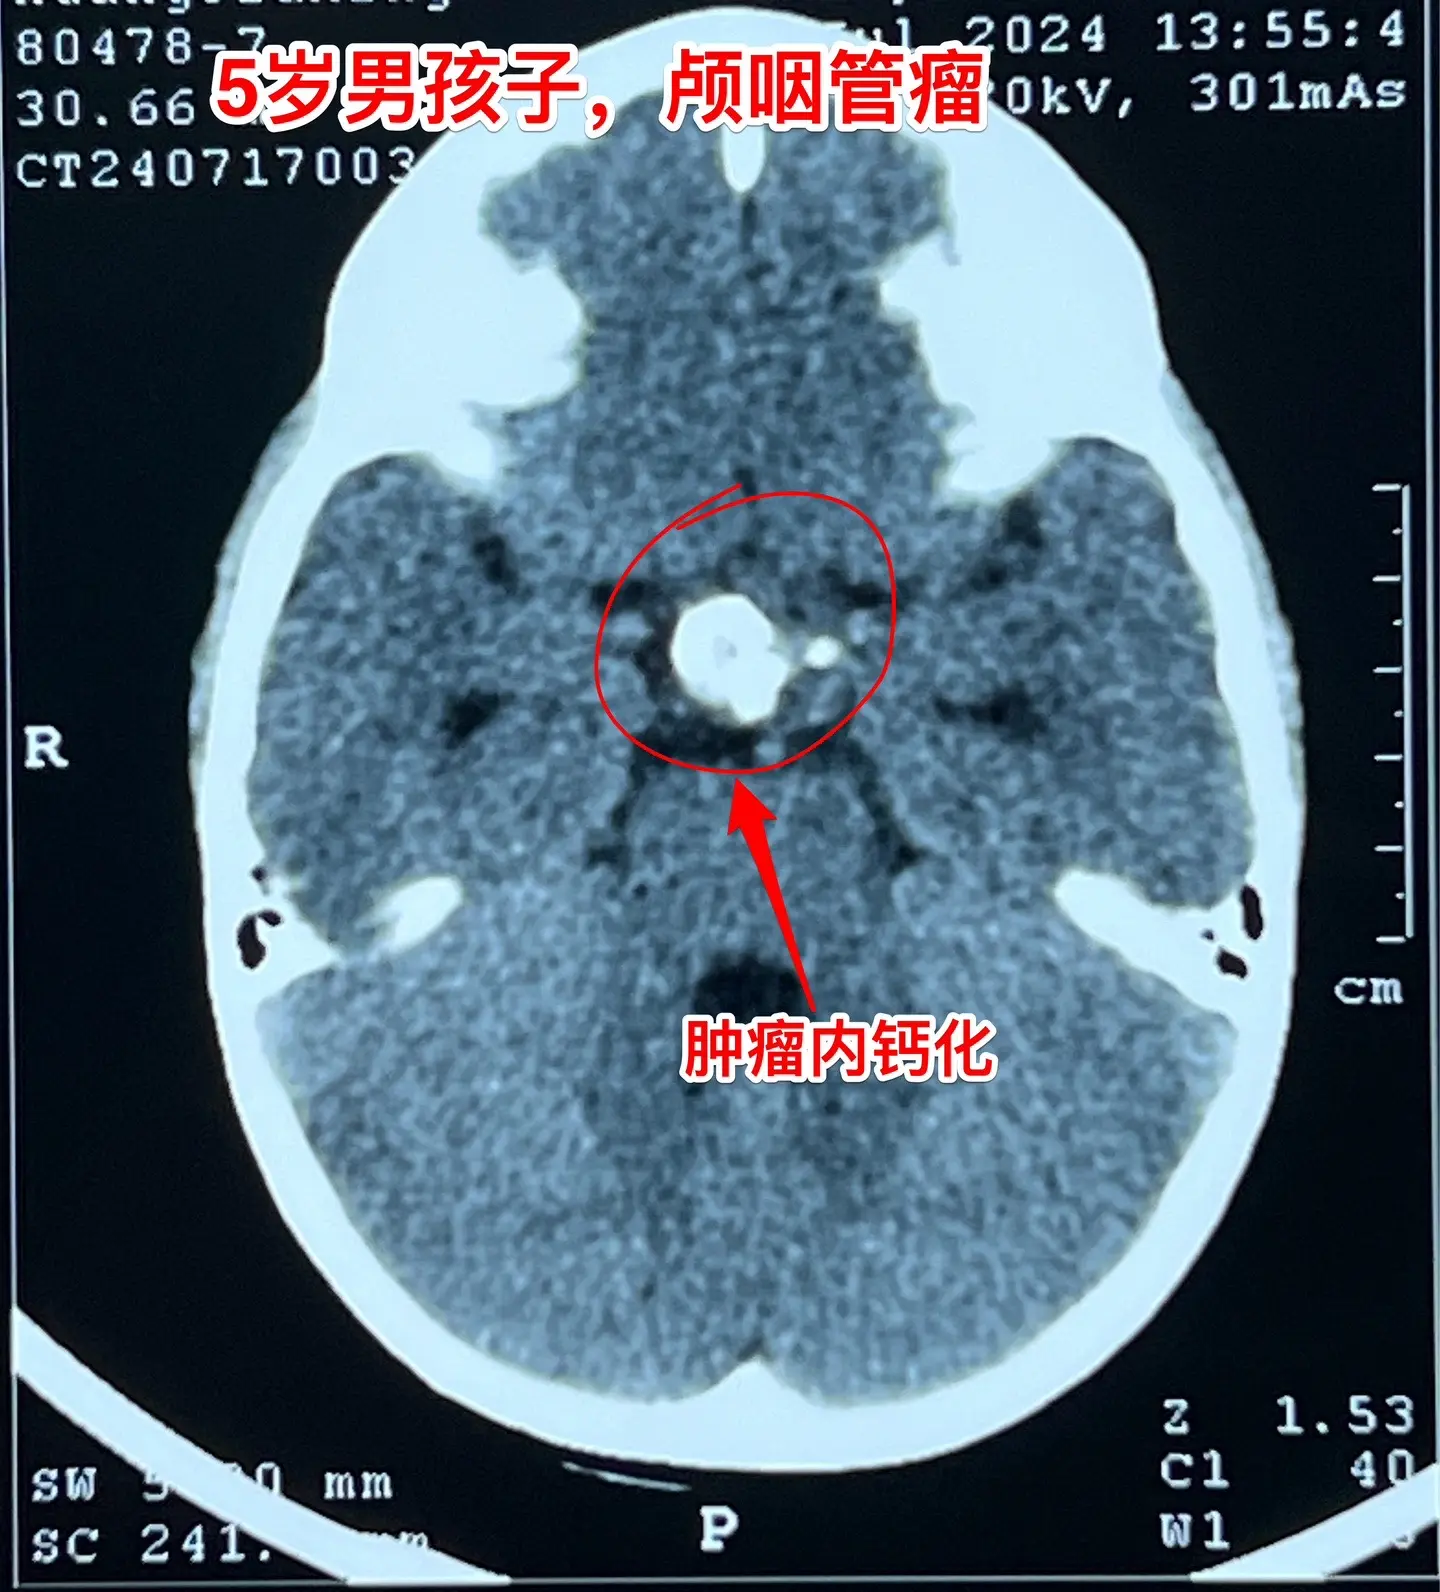

一天两台颅咽管瘤手术对于我们科是常态!7月24日我们科按常规安排了两台颅咽管瘤:第一个5岁男孩子,广东人,因为身高增长缓慢发现了颅咽管瘤。第二个是25岁的三门峡市男性,因为视力下降发现了颅咽管瘤。两个手术都顺利完成。 这样的手术安排对于我们三博脑科医院神经外科八病区来说几乎是常态。有时候一天完成两台复发颅咽管瘤手术,最多的时候一天完成三台颅咽管瘤手术。应该说如果一天只作一个颅咽管瘤手术是比较合理的,一天作两个劳动强度是很高的,不值得提倡。